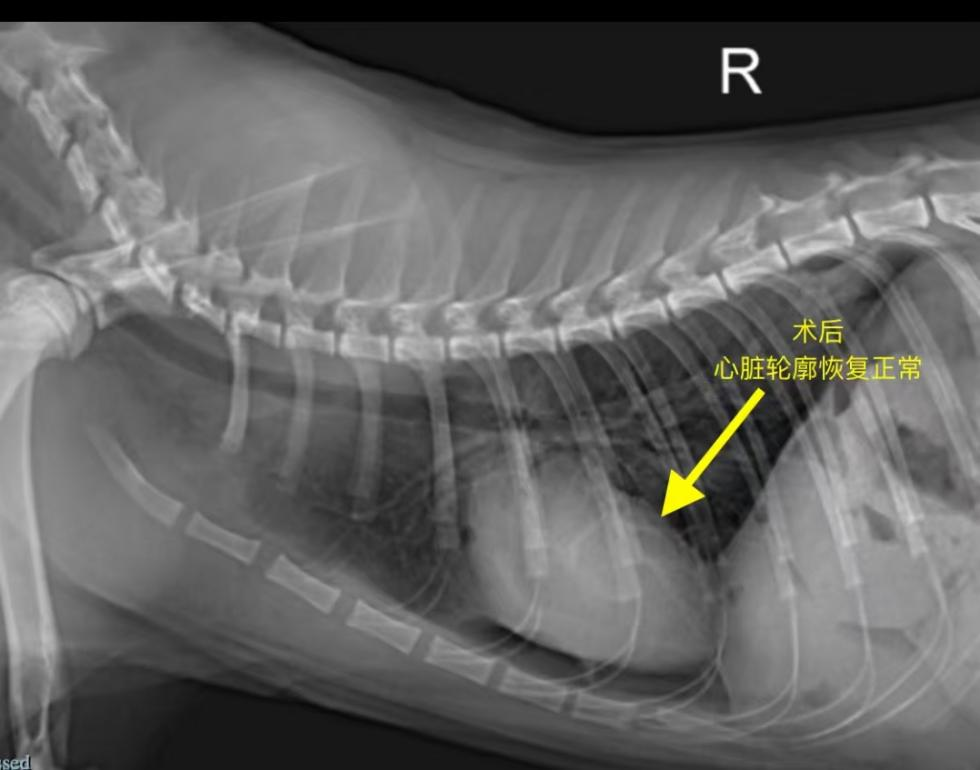

通过分离肝脏组织、修复膈肌缺损,成功恢复正常的胸腹腔解剖结构。